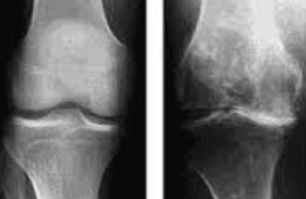

관절염과의 관계

무릎 연골 손상이 진행되면 결국 퇴행성 관절염으로 발전하게 됩니다. 초기 연골 손상 증상이 관절염의 전단계 증상으로 볼 수 있으며, 조기 발견과 치료가 관절염 예방에 매우 중요합니다.